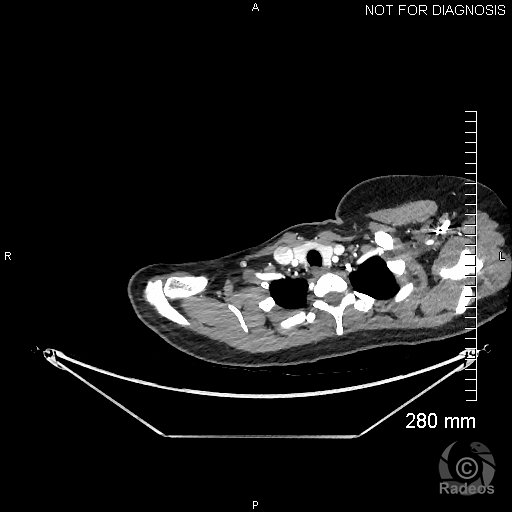

Aspect IRM d'une fibromatose profonde de la paroi abdominale. Découverte fortuite d'un angiome hépatique gauche.